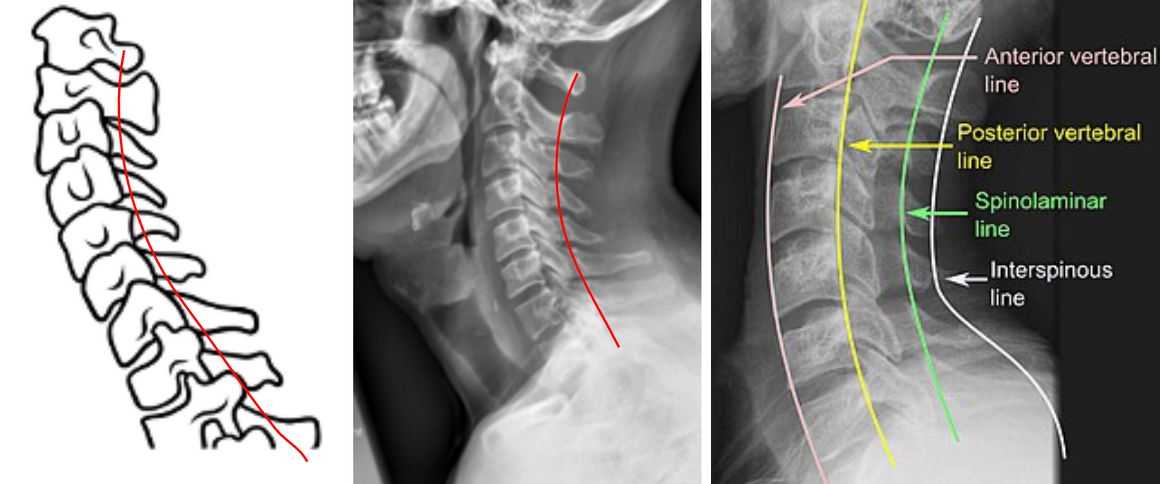

The Spinolaminar Line is a radiographic reference line used to assess posterior cervical alignment and detect subluxation, dislocation, or instability.

It is drawn along the junction between the laminae and spinous processes (the spinolaminar junction) of consecutive cervical vertebrae on a lateral cervical spine X-ray.

A smooth, continuous curve from C1 to C7 represents normal posterior alignment. Any step-off or discontinuity indicates possible vertebral displacement, facet dislocation, or fracture, particularly in traumatic injuries.

This line complements George’s Line (posterior vertebral body line) as part of a systematic three-line evaluation for cervical stability.

• The spinolaminar junction lies where the lamina meets the base of the spinous process, appearing as a continuous posterior cortical shadow.

• Draw a smooth, curving line connecting these junction points from C1 through C7.

The Spinolaminar Line, along with George’s Line (posterior vertebral line) and the anterior vertebral body line, forms the three-line cervical alignment assessment on lateral X-ray.